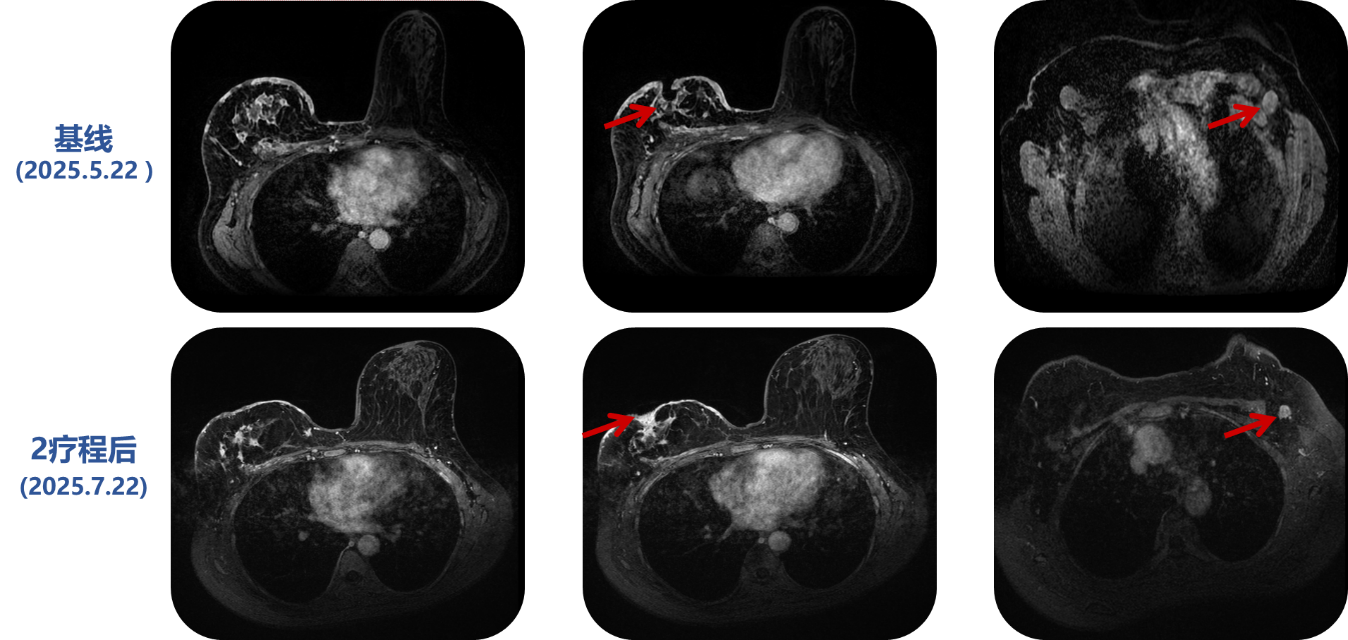

疾病进展 (2025.05.22):患者病情急剧恶化,右乳病灶破溃增大,皮下结节增多。

治疗方案:基于PIK3CA突变结果,采用伊那利塞 (9mg qd) + 氟维司群 (500mg q4w)靶向治疗。

疗效评估(2025.7.22):治疗2疗程后,疗效评估为PR 。患者胸壁破溃病灶基本愈合,肺转移灶消失。

最新进展(2025.8.21): 完成3疗程治疗后,胸壁破溃病灶在原有基础上进一步愈合,创面持续改善。目前PFS持续中。

回到本病例,虽然患者处于四线治疗的危重阶段,但其对伊那利塞的响应速度和深度(2疗程后肺部病灶CR,胸壁破溃愈合),生动地展示了当抓住主要驱动基因并予以强效抑制时,即使是后线患者也能获得石破天惊的卓越疗效。这从实践层面印证了INAVO120研究的结论:对于携带PIK3CA突变的患者,PI3Kα抑制剂是不可或缺的关键药物。